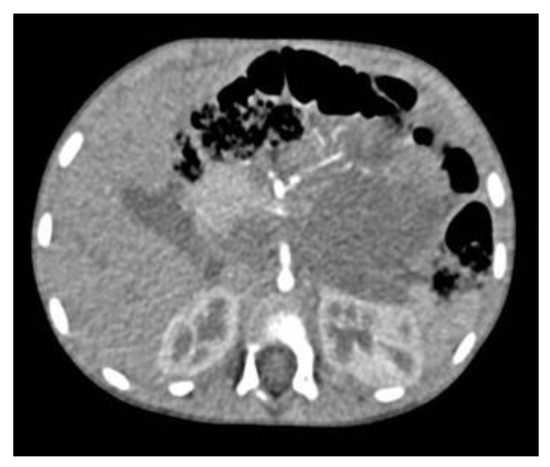

2. Technical Procedure